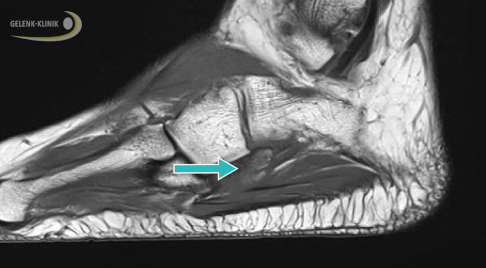

Dabei hat die DVT mehrere Vorteile: Sie ist nicht nur strahlungsärmer als das konventionelle Röntgen. Mit ihr lassen sich dreidimensionale Bilder anfertigen, auf denen man die Knochenoberfläche, die Gleitrinne der Sehnen und eventuelle Knochenerhebungen gut erkennen kann. Häufig wird auch eine Kernspintomographie durchgeführt. Sie ermöglicht eine besonders gute Beurteilung der Sehne und des umliegenden Gewebes. Risse, Luxationen und Entzündungen der Sehne können damit gut unterschieden werden.